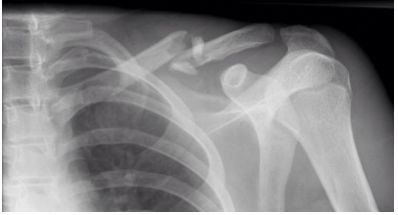

59 某 17 歲男孩,某日騎單車跌倒,著地時左手臂直接撐地,旋即發生劇烈疼痛,經送醫檢查發現其 X 光片如圖所示,下列敘述有幾項正確?①左拄骨骨折 ②多發生於中 1/3 處 ③大多使用“∞”字繃帶 固定 ④患者常以健手托著患側肘部,以減輕上肢重量牽拉 ⑤幼兒多見 (A)2 (B)3 (C)4 (D)5